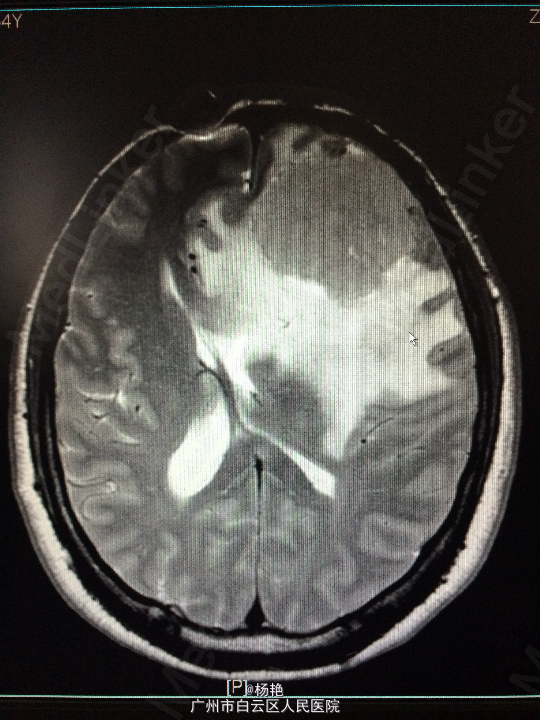

主诉:反复头痛2年加重1周 病史:患者诉两年前无明显诱因反复出现头晕头痛不适,近一周来症状加重,无恶心呕吐、无行走不稳、肢体乏力、意识障碍等。遂至当地医院诊治,行头颅CT、MR检查均提示颅内占位,良性可能性大,考虑脑膜瘤。今患者为求进一步治疗而入我院。

查体:神经系统查体未见明显异常 辅助检查:头颅MR提示:左侧额叶区域较大类圆形肿物,多考虑脑膜瘤可能;大脑前动脉及中动脉受压,中线偏移。

诊断:左额叶脑膜瘤 处理:在静脉全麻下行左侧额底脑膜瘤切除术,术后病理提示:脑膜瘤